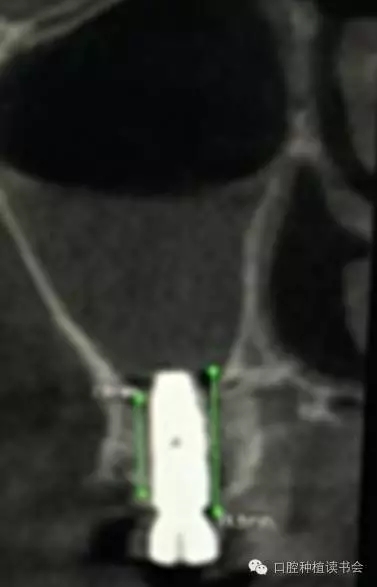

雖然牙槽脊垂直、水平吸收的程度幾乎相當(dāng),但是由于上頜后牙牙槽脊寬度較大,后牙區(qū)經(jīng)常出現(xiàn)圓鈍的、較寬的牙槽骨狀態(tài),臨床表現(xiàn)為剩余牙槽骨高度(Residual Bone Height,RBH)不足。在個別情況下,由于嚴(yán)重牙周病、根尖病等因素的影響,也會使牙槽脊水平寬度不足,表現(xiàn)為刃狀牙槽脊。上頜后牙一般為多根牙,當(dāng)牙周病和根尖病到一定程度后,磨牙才開始松動導(dǎo)致不能保留,又因上頜牙槽骨骨密度較低,在有些病例,牙槽脊重度吸收,RBH甚至不足1mm(圖1)。

▲(圖1)